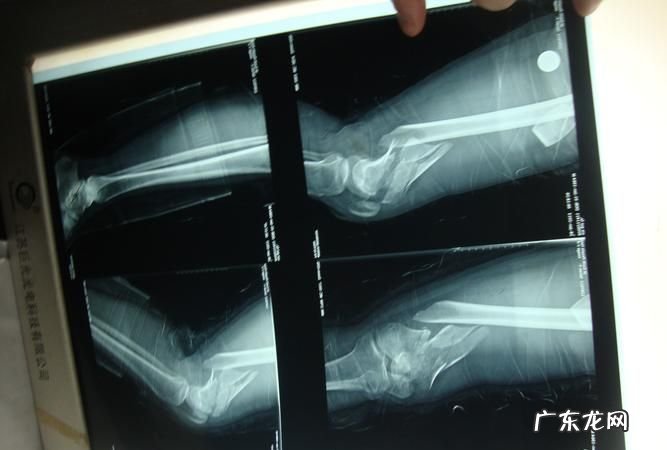

如果遇上工伤粉碎性骨折的情况,先做一个工伤鉴定,工伤认定以后,经过治疗伤情相对稳定后申请劳动能力鉴定,评定伤残等级 。根据《职工工伤与职业病致残程度鉴定标准》(GB/T 16180-2006),身体各部位骨折愈合后无功能障碍是十级,骨折内固定术后,无功能障碍者是九级 。具体情况,最终以劳动能力鉴定为准 。如果能评为九级伤残,工伤待遇如下:

根据致残程度鉴定标准,身体各部位骨折愈合后无功能障碍是十级,骨折内固定术后,无功能障碍者是九级 。具体情况,最终以劳动能力鉴定为准 。如果能评为九级伤残,工伤待遇如下: